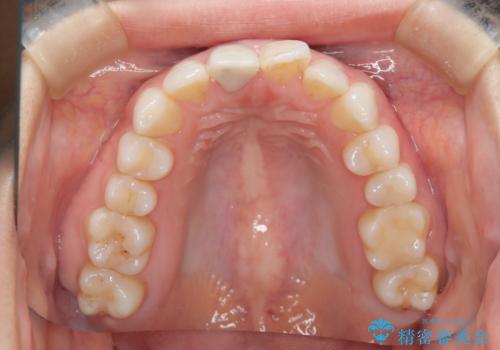

根管治療と並行して矯正を マウスピース治療

- 前歯のガタつき、変色を主訴に来院された患者様です。術前診査のCT撮影にて、変色した前歯の根の先に病巣があることが判明しました。そこで、マウスピースによる矯正治療と、前歯の根管治療、かぶせ物のやり直し治療を並行して行いました。